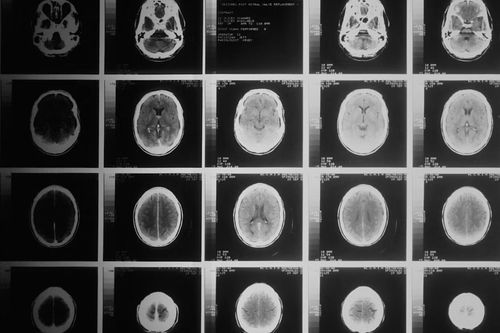

Prawie 8 tys. skanów mózgów

Badacze przeanalizowali 7876 skanów z rezonansów magnetycznych mózgu, spośród których 4078 było kobiecych, a 3798 męskich. Celem było określenie ilości różnic w budowie mózgu między płciami i odniesienie ich do statystycznej ilości nierówności w danym kraju.